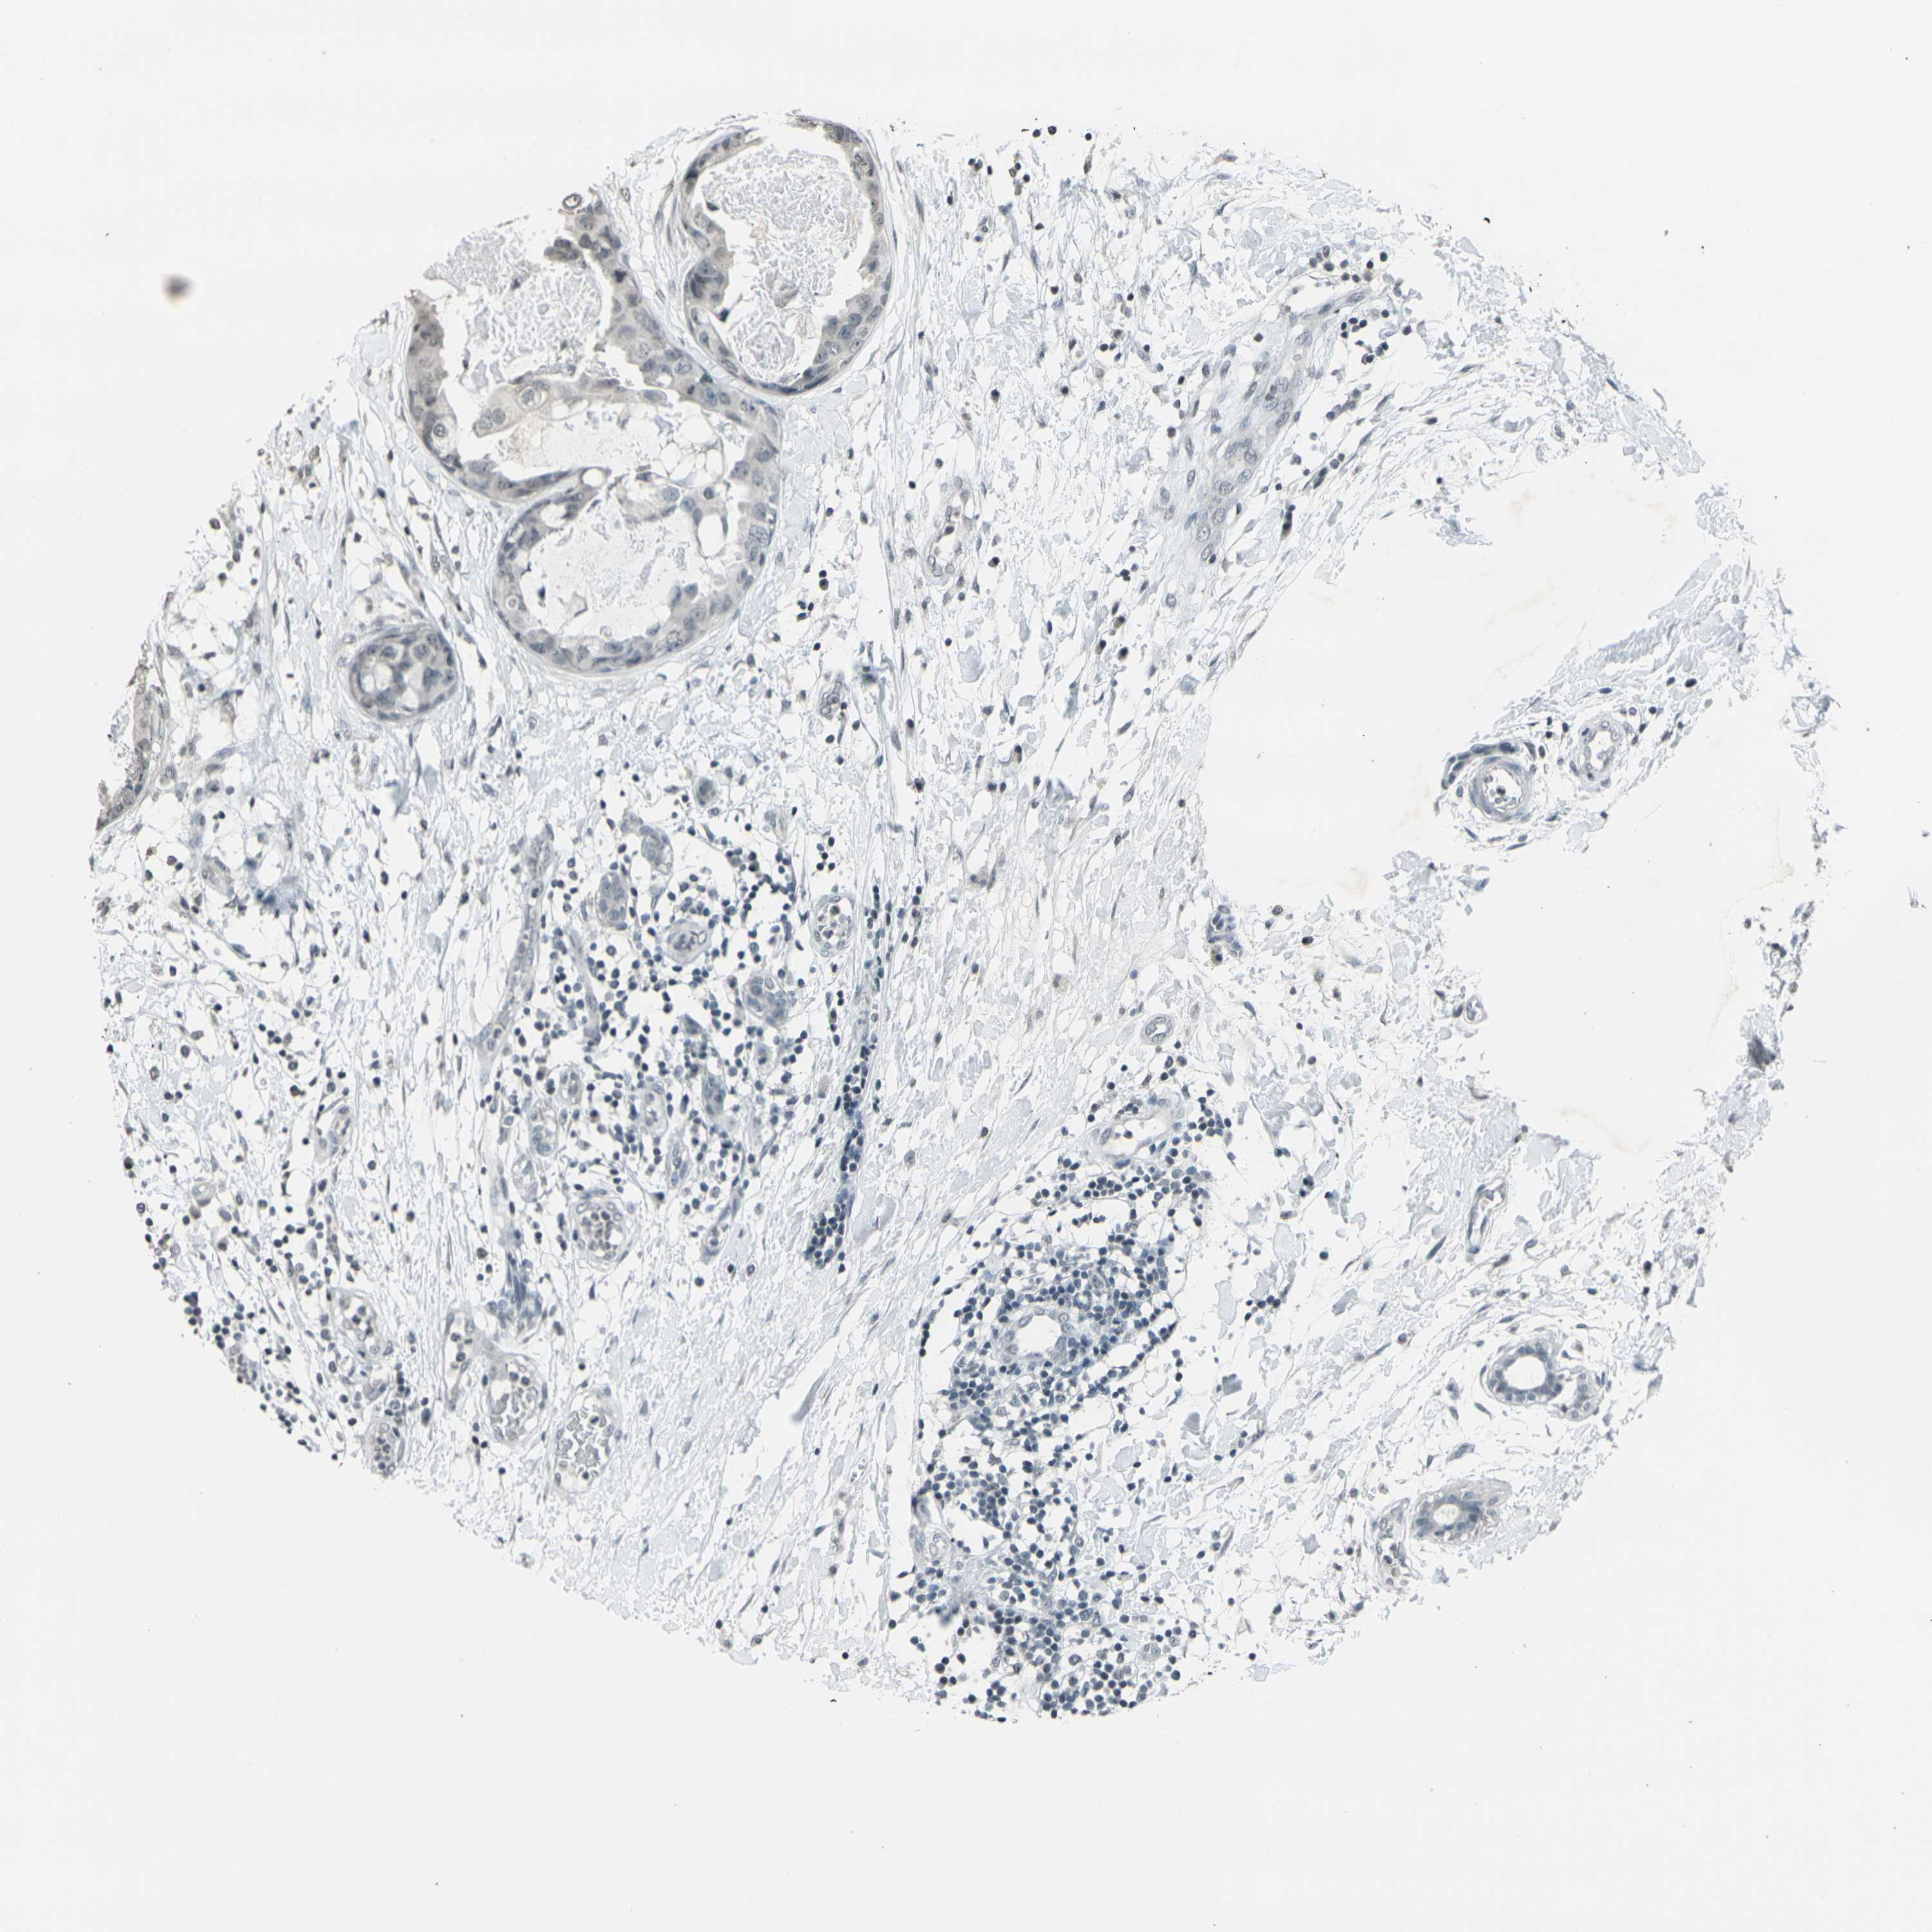

CANCER BREAST CANCER Show tissue menu

BRCA TCGA BRCA VALIDATION PROTEIN EXPRESSION

Breast cancer

Human cancer

PRPF8 is not prognostic in Breast Invasive Carcinoma (TCGA)